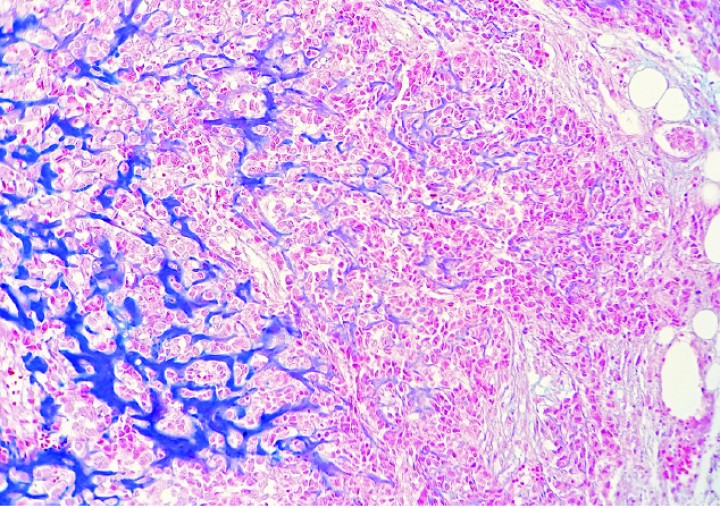

En las 4 cobayas evaluadas con azul alcián, la matriz extracelular se tiñó de color azul intenso con excepción de las zonas osificadas, que eran eosinófilas pálidas a rojas (Figs. 9-12). Las células mostraron un núcleo de redondo a elíptico o irregular con la cromatina laxa o granular, 0-3 nucléolos ocasionalmente prominentes y una cantidad media de citoplasma eosinófilo o basófilo pálido variablemente vacuolizado. La anisocitosis, anisocariosis, pleomorfismo y anaplasia eran generalmente moderados y se distinguían entre 0-3 mitosis por campo de 40 aumentos. En dos cobayas se apreció embolismo de células neoplásicas en vasos sanguíneos y en 3 casos se observaron focos de metástasis pulmonar (Fig. 12). Los niveles de sección evaluados de las múltiples masas de la extremidad posterior hasta zona lumbar de la cobaya 4 no revelaron tejido linfoide, motivo por el cual no se pudo demostrar de forma definitiva que alguna de ellas correspondiera a metástasis en linfonodos regionales. En algunos casos, la neoplasia mostraba amplias áreas de necrosis y/o hemorragia aguda, además de pequeños focos de hemosiderosis.

<p>Cobaya 4. Imagen microscópica de una zona altamente celular de un condrosarcoma con transición a una zona de producción de matriz cartilaginosa (azul). (Azul alcián, x220).</p>

Figura 9

Cobaya 4. Imagen microscópica de una zona altamente celular de un condrosarcoma con transición a una zona de producción de matriz cartilaginosa (azul). (Azul alcián, x220).

<p>Cobaya 2. Imagen microscópica de una zona rica en matriz cartilaginosa (azul) de un condrosarcoma con depósito incipiente de osteoide (flechas) en un proceso de osificación endocondral del cartílago neoplásico. (Azul alcián, x220).</p>

Figura 10

Cobaya 2. Imagen microscópica de una zona rica en matriz cartilaginosa (azul) de un condrosarcoma con depósito incipiente de osteoide (flechas) en un proceso de osificación endocondral del cartílago neoplásico. (Azul alcián, x220).

<p>Cobaya 2. Imagen microscópica de una zona de osificación endocondral prominente (asteriscos) de un condrosarcoma con depósitos no osificados de matriz cartilaginosa (cabezas de flecha). (Azul alcián, x480).</p>

Figura 11

Cobaya 2. Imagen microscópica de una zona de osificación endocondral prominente (asteriscos) de un condrosarcoma con depósitos no osificados de matriz cartilaginosa (cabezas de flecha). (Azul alcián, x480).

<p>Cobaya 4. Imagen microscópica de metástasis pulmonares de un condrosarcoma que producen abundante matriz cartilaginosa (azul). (Azul alcián, x220).</p>

Figura 12

Cobaya 4. Imagen microscópica de metástasis pulmonares de un condrosarcoma que producen abundante matriz cartilaginosa (azul). (Azul alcián, x220).